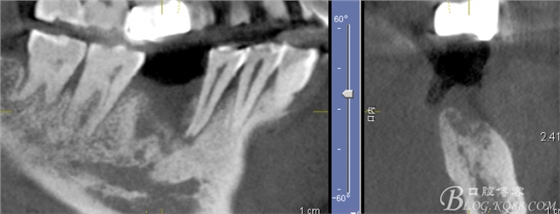

3月后復(fù)查見(jiàn)C5根尖有吸收

C6骨吸收明顯

患者希望功能上恢復(fù),要求種植,不接受根管治療風(fēng)險(xiǎn)